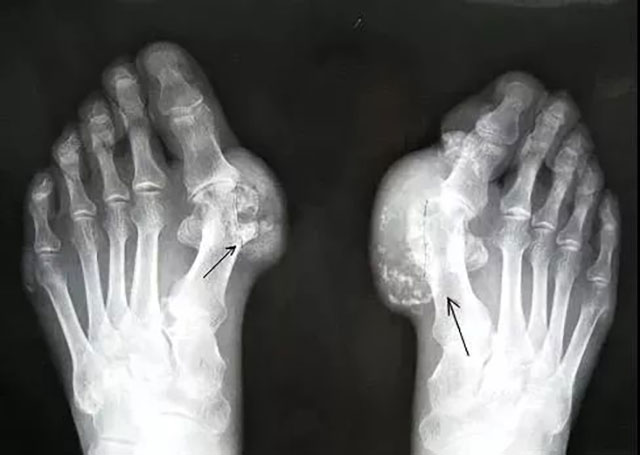

相较于王先生的急性发作,李大爷的症状就有点“触目惊心”了。

一双手因为痛风石堆积逐渐畸形,布满结节,凸起,发作起来更是苦不堪言。

所谓痛风,是由尿酸盐沉积导致的一种晶体相关性关节病。就好比水里的盐浓度太高了,慢慢被析出来就形成“尿酸结晶”,导致痛风。

因为海鲜和动物内脏都是高嘌呤食物,而啤酒本身就含有大量的嘌呤,加上酒精进入人体后会代谢产生乳酸,乳酸会抑制肾小管分泌尿酸,使肾脏排泄尿酸的能力降低,尿酸可析出结晶,沉积在骨关节、肾脏和皮下组织等,造成组织病理学改变,导致痛风性关节炎、痛风肾和痛风石等。